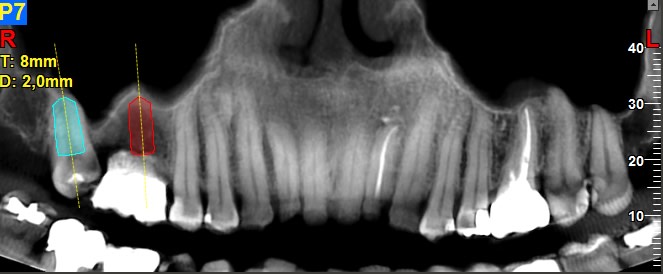

exo 18, sinus lift, implant 16 17

exo 18, implant 16 et 18, bridge 16-18. Sinus lift en option.

Par contre est ce que la mésialisation de la 18 est possible même si le sinus plonge au niveau de l'édentement de la 17 ancien et qu'il n'y a pas d'os en mésial ? Ça va se remanier tout seul ?

Bonsoir, je ferais comme sur l'image n°6, c'est à dire extraction 18, implant en 16 droit, implant angulé en 18 et prothétiquement une 16 et une 17. Pas de sinus, pas d'ortho. Voir 48 qui risque de poser des problèmes au niveau occlusale.

Juste pour info il n'y a pas de contre indication particulière à bouger une dent qui est contre le sinus. Dans certain cas ça peut ralentir le mouvement mais c'est plus ou moins tout. Clairement pas un soucie si il y a un implant.

Un de mes tout premiers cas.

Extraction de 16 et 26, 17 et 27 étant clairement contre le sinus.